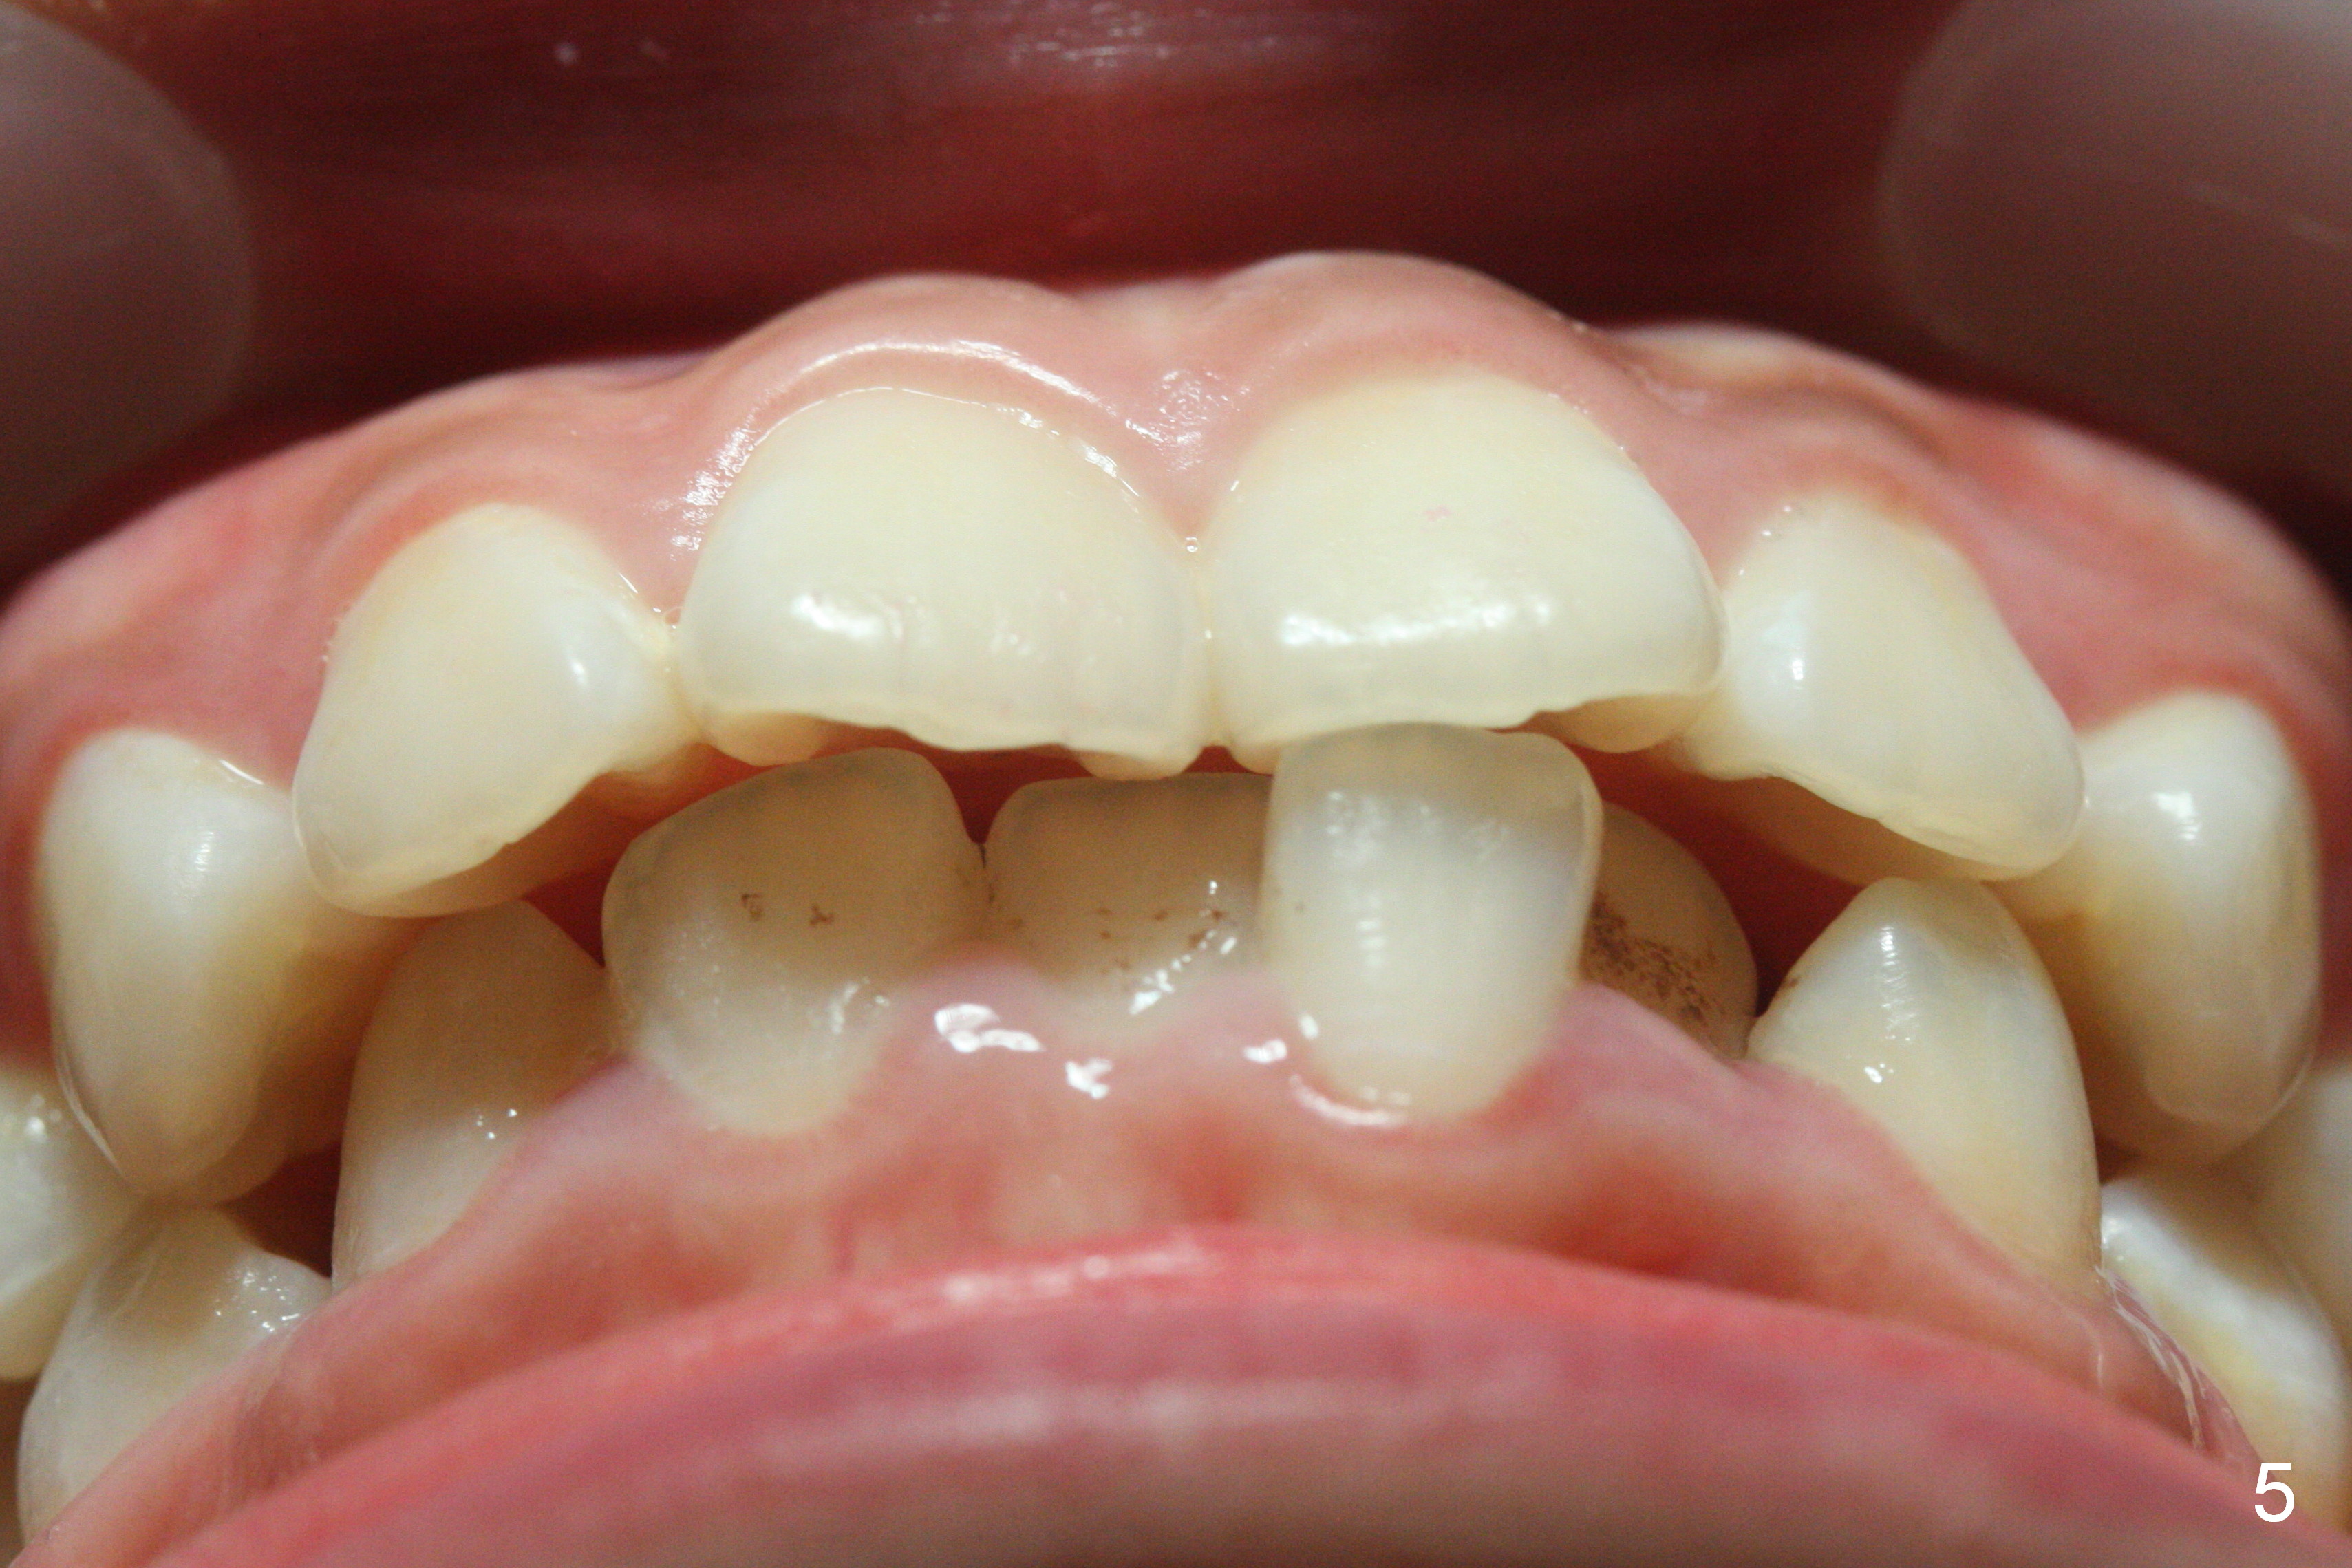

A 17-year-old woman will return for bracketing after caries control and deciduous tooth (Fig.6 arrowheads) extraction. Her profile is slightly protrusive (Fig.1,2). Crowding is more severe in the left posterior region (Fig.4) than the right one (Fig.3). The anterior crowding is also severe (Fig.5). Proximal reduction and use of power chain for constriction will be used instead of extraction of 4 bicuspids. Third molar extraction may have to be done prior to banding, especially for the lower right 2nd molar (Fig.7).

By looking at preop models (Fig.8-13), do you think whether extraction is a better option than non-extraction? Class II occlusion on the right (Fig.8), Class I on the left (Fig.10). With extraction of the 1st bicuspids, the posterior occlusion could be normal with further anterior protrusion (Fig.11). The upper arch is rounded (Fig.12); without extraction, the arch may turn out to be U-shaped. The lower arch is more crowded (Fig.13). Without space, the lower right 2nd molar may not be uprighted (Fig.7).